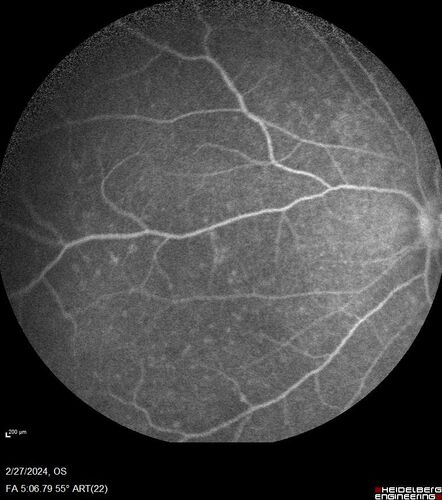

Syphilitic Chorioretinitis

41 year old man with vision loss for five days left eye. VA 20/32, 20/200

Syphilitic Chorioretinitis Both Eyes